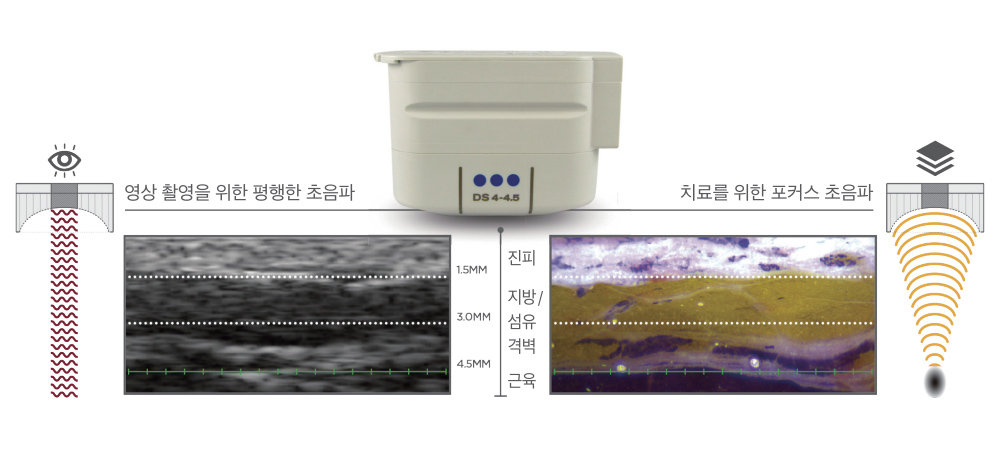

특허받은 실시간 초음파 영상기술(DeepSee™)은 비침습적으로 어느 부위를 시술하고 있는지 볼 수 있는 특화된 기술입니다.

그에 맞추어 안전하고 효과적으로 시술할 수 있으며 숙련된 의료진의 이해를 바탕으로 보다 정밀하게 시술합니다.